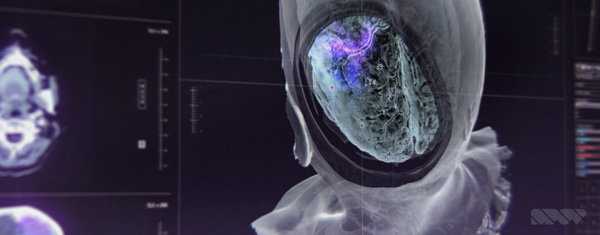

Nevertheless, instead of looking creepy or frightening, the results are strangely beautiful and pull the viewer toward the inner world of brains, bones and blood vessels. This look is no accident. SPOV’s main pipeline is based on Cinema 4D used together with After Effects for compositing – tools SPOV has used for years on nearly all projects and which nearly all of their artists are very familiar with.

Allen said, “For some of the artists here, Cinema 4D plus Creative Cloud software, mainly After Effects, sometimes Photoshop, are the means to create nearly anything. Over time, some have developed skills in 3D software like Maya, or ZBrush as a dedicated sculpting tool. But on ‘Doctor Strange’, although we needed diverse 3D effects, textures and modelling, only Cinema 4D and After Effects were used for everything, including a huge amount of detailed sculpting on some of the assets. We also successfully pushed Cinema’s Proximal Shader to create a smooth, adjustable ghosted effect.

“We could use soft, controllable Boolean operations for the ghosting of hard surfaces. In addition we could render out and animate a black-and-white map precisely determining the cut away areas. Passes were rendered and exported from Cinema 4D, and then layered up in After Effects for compositing.” A nice example of how this looks in the film is in the images above and at the top of this article, showing a portion of the skull cut away to reveal the brain inside.

Looking authentic and attractive in isolation is one thing, but Allen is especially pleased with the way the images look in the movie – not just on darkened sets where they glow against a black background but also in fully lit scenes where they integrate completely into the everyday world of the hospital. “Cinema 4D’s tools don’t get in the way of the creative process," he reflected. "It helps us quickly identify the most efficient route to achieve the result we’re seeking – from revolutionary flying vehicles or fantastic game characters, to something as real as an X-ray or MRI scan – and to cut down on iteration time.” www.spov.tv